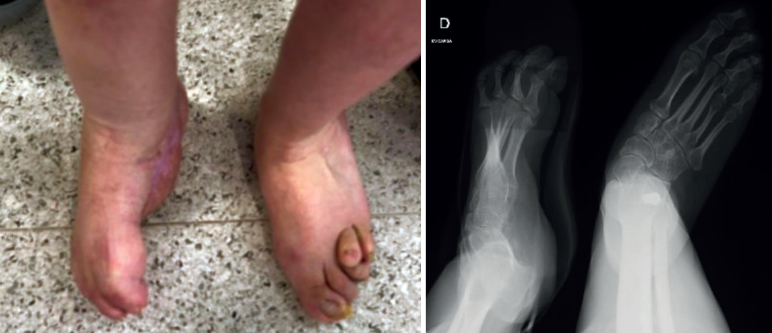

Tras la retirada del fijador y la inmovilización, se autorizó la carga. La paciente presenta un pie plantígrado e indoloro sin complicaciones asociadas (Figura 4).

Al año de la cirugía, la paciente se encuentra deambulando de manera autónoma y sin ayudas, con un buen resultado global a nivel clínico y radiológico.

Figura 4. Pie corregido.